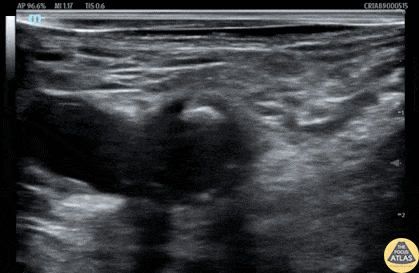

A 90s year old female presented with hip pain after a fall off of a couch. Her workup confirmed an isolated femoral neck fracture in addition to acute metabolic encephalopathy and dementia. To provide analgesia while avoiding further sedation medications given her altered mental status, a fascia iliaca block was offered. After an informed consent conversation with the patient’s MDPOA, the block was performed as shown here. The needle is seen entering from the lateral aspect, injecting anesthetic along the fascia iliaca lateral to the femoral neurovascular bundle. This patient had improved pain and was able to be admitted for further management. Dr. Cheyenne Smith, PGY3 Denver Health Residency in Emergency Medicine